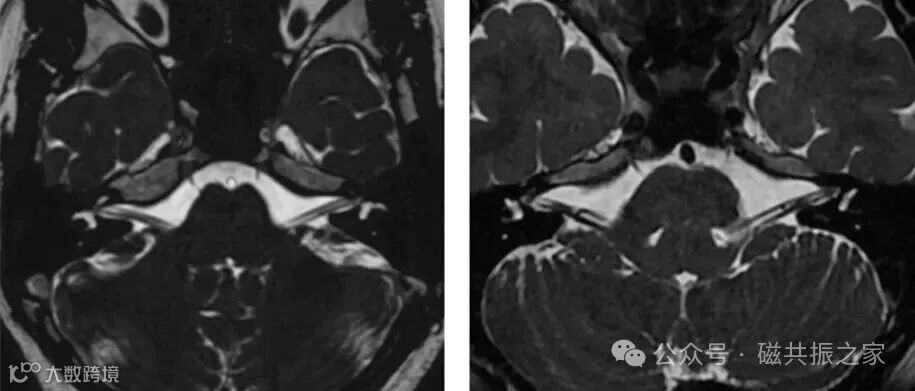

如在扫描内听道(IAC)时,建议使用重T2参数扫描定位像,可突出含水丰富组织的信号对比,以便于更高的识别和定位,如上图△。

如定位像不足以完成后续的精准定位参考和大范围评估有无占位性病变,可首先扫描一个范围较广的冠状位重T2序列(如上图△)或全脑的3D T1WI序列,可在此序列图像上找到目标结构后,再进行精准定位扫描。